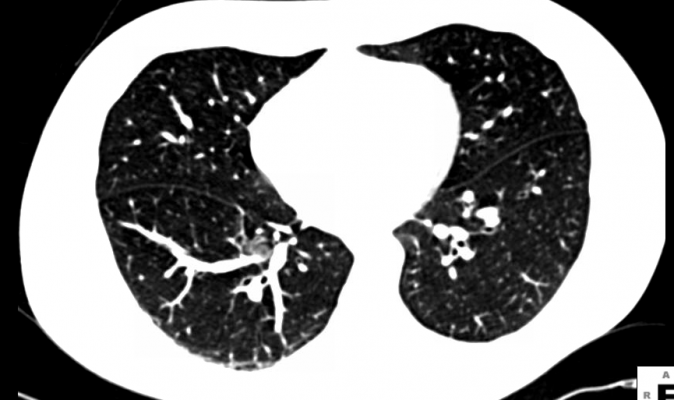

These concerns echoed those of the ACR and more than 80 patient advocacy groups, medical associations and healthcare systems. These groups recently warned CMS that proposed cuts to reimbursement for LDCT shared decision making sessions and LDCT scans of 64 and 44 percent, respectively, may scuttle recently established screening programs and deter local providers from starting screening programs.

CMS moved to provide lung cancer screening coverage for high-risk patients in 2016, largely based on United States Preventive Services Task Force (USPSTF) recommendations. However, the proposed reimbursement cuts would likely restrict screening to large metropolitan hospitals. Those in suburban and rural areas may face longer commute and wait times to be screened — if they can gain access to screening at all.

More than 220,000 people will be diagnosed with lung cancer this year. Nearly 160,000 people will die from the disease — more than from breast, colon and prostate cancers combined.